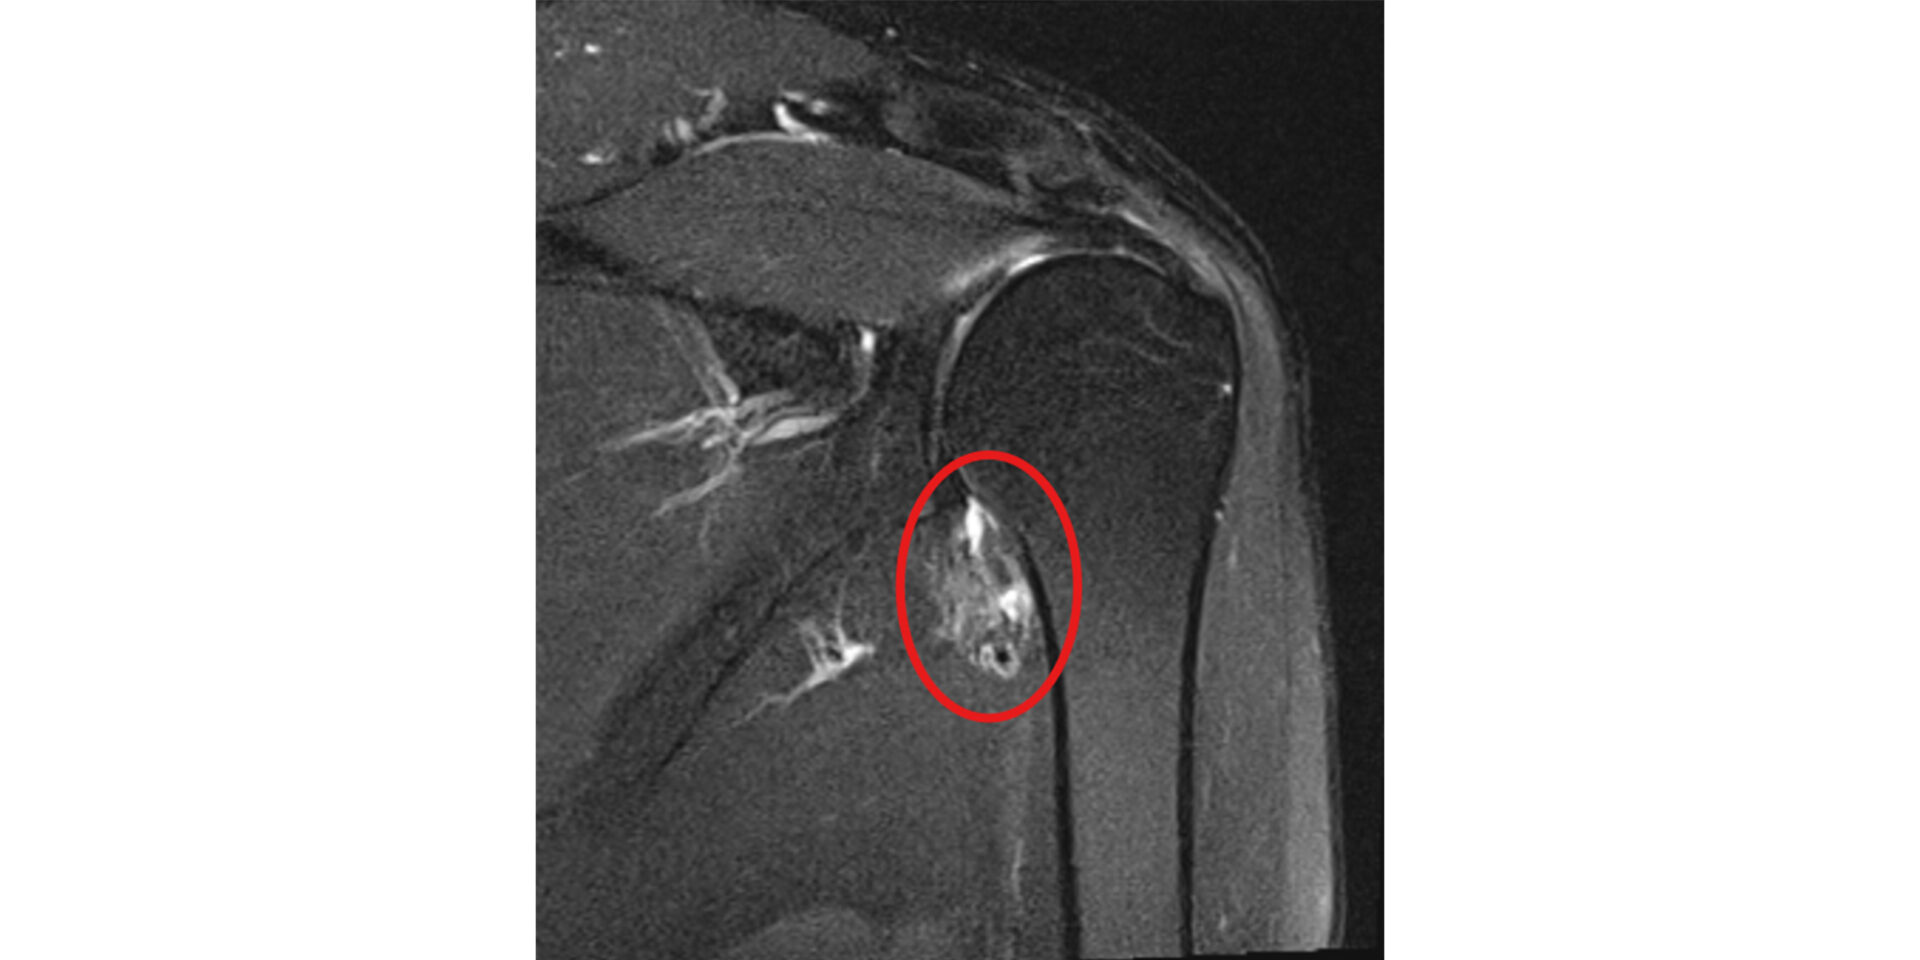

MRI(磁気共鳴画像)

MRIは、腱板断裂や肩関節周囲炎の診断において特に有用な検査です。

腱板の断裂の有無・大きさ・範囲、断裂した腱の種類、周囲の筋肉の状態まで、レントゲンでは確認できない詳細な情報を得ることができます。

治療方針を決める上で非常に重要な検査です。 -